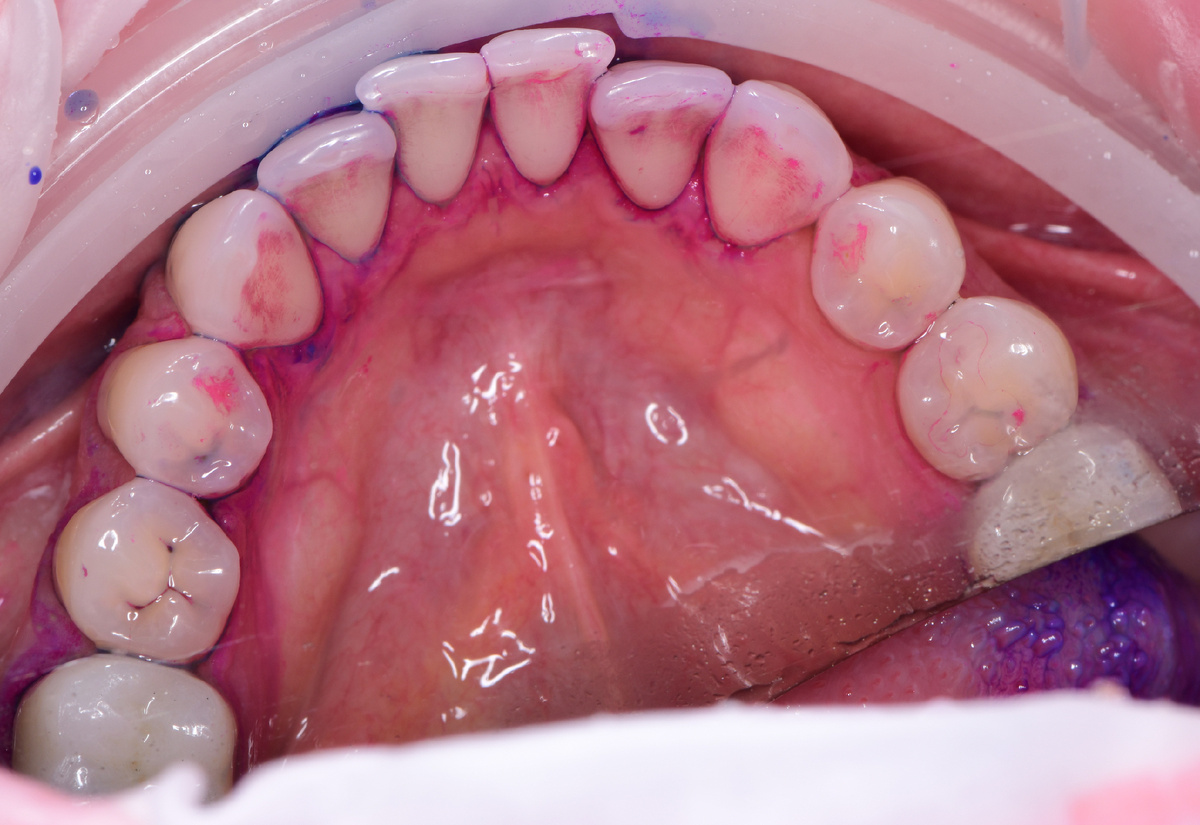

Ключевой фактор появления кариеса и развития периимплантитных и пародонтальных инфекционных процессов — наличие биопленки на наших зубах 👋 Знакомьтесь, наш пациент Елена, 45 лет, обратилась для проведения поддерживающей профессиональной гигиены 👄 Проводим индикацию зубного налета, чтобы показать и продемонстрировать пациенту пигментированные области скопления налета (биопленки) За счет окрашивания нам удастся определить, а в дальнейшем оптимальным образом устранить, зубные отложения Существует три градации по оттенку окрашивания биопленки: Розовый ➡️ Синий ➡️ Зеленый В розовый цвет окрашивается тот налет, который у нас скопился сегодня, т.е. в течение дня. В синий и зеленый цвета окрашивается застарелый налет, который у нас откладывается в течение двух-трех дней. Зеленый налет у пациента не так ярко представлен, но все-таки есть. В области контактных пунктов в области моляров зубов на верхней челюсти. ❗️ В розовый, синий и зеленый цвета окрашиваются только мягкие зубные отложения, ко

Проводим индикацию зубного налета, чтобы показать и продемонстрировать пациенту пигментированные области скопления налета (биопленки)

За счет окрашивания нам удастся определить, а в дальнейшем оптимальным образом устранить, зубные отложения

Существует три градации по оттенку окрашивания биопленки:

Розовый ➡️ Синий ➡️ Зеленый

В розовый цвет окрашивается тот налет, который у нас скопился сегодня, т.е. в течение дня.

В синий и зеленый цвета окрашивается застарелый налет, который у нас откладывается в течение двух-трех дней. Зеленый налет у пациента не так ярко представлен, но все-таки есть. В области контактных пунктов в области моляров зубов на верхней челюсти.

❗️ В розовый, синий и зеленый цвета окрашиваются только мягкие зубные отложения, которые еще не успели минерализоваться

Минерализованные (затвердевшие) зубные отложения обычно лежат под мягким налетом. Соответственно, уже по опыту видим, что под мягким налётом внизу, на язычной поверхности нижних зубов (см. фото ниже 👇), есть минерализованный налет. Его нужно будет убирать либо ультразвуком, либо, если он ещё не до конца минерализовался, удастся убрать с помощью порошка.

Очень часто минерализованный налет образуется на поверхности нижних зубов, особенно если есть скученность, потому что там сложнее всего вычистить наш налет. Мы не дочищаем эти поверхности, т.к. иногда физически не можем там тщательно пройтись. Налёт там лежит долго и начинает минерализоваться.

По состоянию окрашенных зубов видим то, что Елена действительно хорошо чистит зубы. Но все-таки есть области на контактных поверхностях зубов, которые не дочищаются.

Рекомендуем использовать зубную нить для того чтобы не было такого большого скопления налета на этих поверхностях

По реставрациям мы уже видим, что ранее зубы уже лечили и именно на контактных поверхностях. Будет обидно допустить образование вторичного кариеса под этими пломбами.1️⃣ Снятие налёта с помощью Airflow